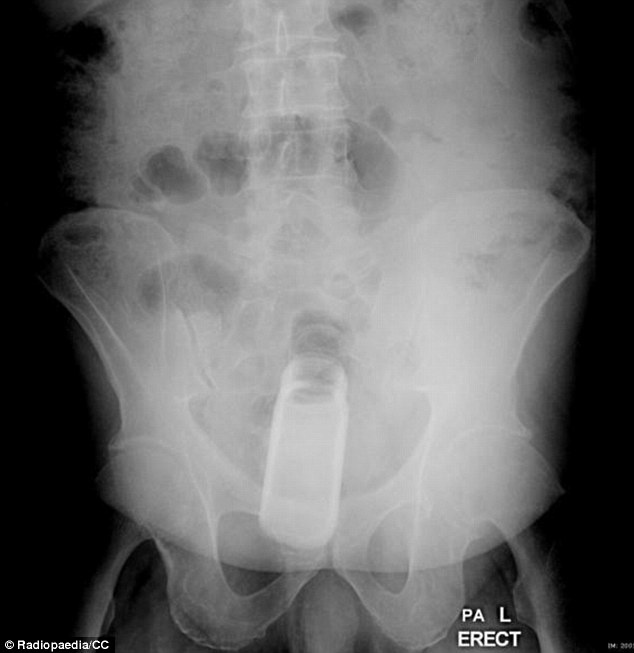

| Dị vật trong ảnh là một chai nước. |

| Bác sĩ rất ngạc nhiên khi thấy chai khử mùi mắc kẹt trong trực tràng. Các nhân viên y tế chia sẻ hình ảnh X-quang những dị vật lạ lùng trên Radiopaedia - trang web chia sẻ tài liệu dành cho chuyên viên X-quang. |